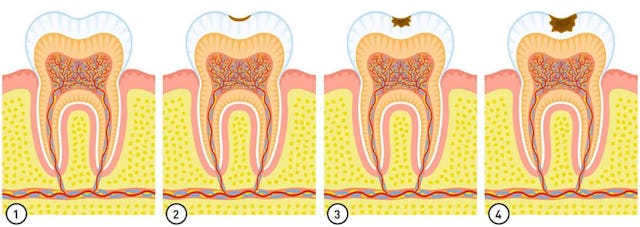

Die oben bereits beschriebene Entwicklung, Bakterien (Plaque) + Zahnstein, welche zur Entzündung und zum Knochenabbau führen, werden hier auf den oberen vier Bilder nochmals verdeutlicht. Auf dem dritten Bild sehen wir deutlich den Knochenabbau in der Höhe und auf dem letzten Bild den vertikalen Einbruch. In diesem Fall sprechen wir von einer schweren Parodontitis (Entzündung des Zahnhalteapparats).

Bild 1: Intakter Zahn ohne Karies

Bild 2 bis 4: Oberflächliche Kariesbildung ohne Gefahr für die Pulpa (Nerv). Diese Karies (Kariesstadium 1+2) kann durch leichtes Abschleifen vollkommen beseitigt werden (im Fall 2+3), und/oder bei sehr guter Pflege remineralisiert sich der betroffene, demineralisierte Schmelz wieder. Bild 4: Diese (noch) harmlose Karies (Kariesstadium 2) kann auch noch bei sehr guter Pflege mit fluorhaltigen Produkten remineralisieren. Es bleibt aber in der Regel ein dunkelbrauner Punkt, bzw. Fleck bestehen. Um diesen aus ästhetischen Gründen zu entfernen bedarf es einer kleinen Komposit-Füllung oder wie hier in diesem Fall einer Fissurenversiegelung.

Bild 5: Diese relativ tiefe Karies hat bereits die Schmelzschicht durchquert und das Dentin erreicht. Wir reden hier vom Kariesstadium 3+4. Diese Karies kann in der Regel noch ohne Wurzelkanalbehandlung durch Abtragen der beteiligten Zahnhartsubstanz (Schmelz und Dentinanteile) beseitigt werden. Die Reparatur kann mittels einer Kompositfüllung, Inlays oder einer Krone erfolgen.

Bild 6: Diese bereits tiefe Karies hat die Zahnpulpa erreicht. Im Volksmund wird die Zahnpulpa oft nur als Nerv bezeichnet. In der Tat handelt es sich aber um einen oder mehrere Nerven, zu- und abführende Blutgefässe sowie Gewebe. Hier ist eine Wurzelkanal-behandlung als Theapie unumgänglich. Als Alternative kann eine Zahnentfernung in Betracht gezogen werden.

Bild 7+8: Die Karies hat wie im Fall des Bild 6 die Pulpa erreicht und hat zusätzlich zu einer Entzündung in der Region des Pulpaaustritts, an der Wurzelspitze geführt. Diese Entzündung führt zu einem lokalen Knochenabbau und ist auf dem Röntgenbild meist sichtbar. Auf einem dreidimensionalen Röntgen ist diese Entzündung besser sichtbar bzw. besser lokalisierbar. Gelegentlich kommt es zur Eiterbildung und einer akuten Pulpitis (Entzündung der Pulpa), welche oft mit heftigen Schmerzen einhergeht. Breitet sich diese Entzündung noch weiter im Knochen aus, reden wir von einem intraossären Abszess. Breitet sich dieser weiter aus und durchbricht den Knochen und weitet sich in die Weichteile (Wange, Mundboden) aus, reden wir einfach von einem Abszess (Wangenabszess, Mundbodenabszess, Gaumenabszess, usw).